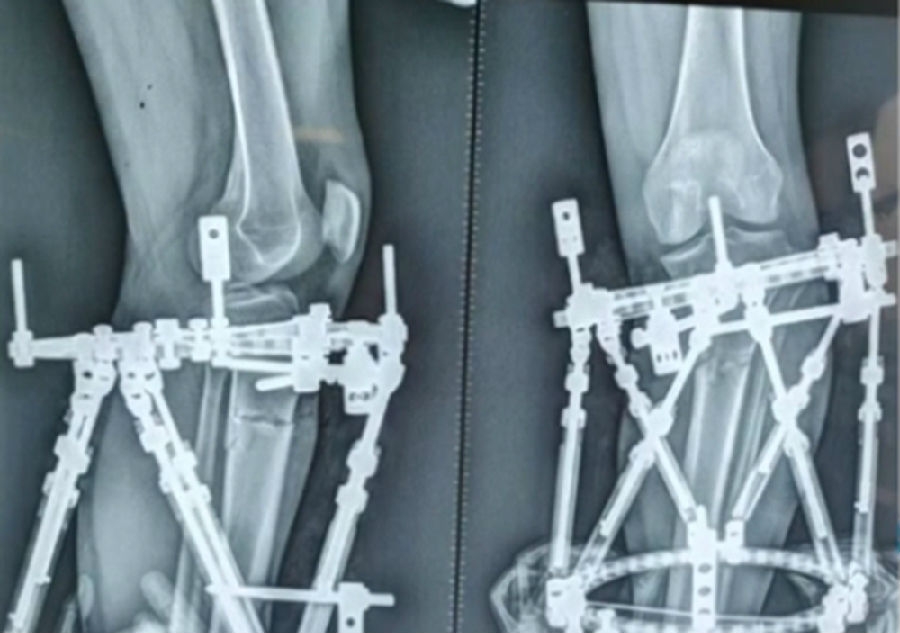

泰勒外固定架缓慢矫正短缩、内翻、前弓、内旋。

术中

该患者截骨后,做MAD矫正,目标MAD=0。患者术后1个月即达到设计的效果。

术后1个月